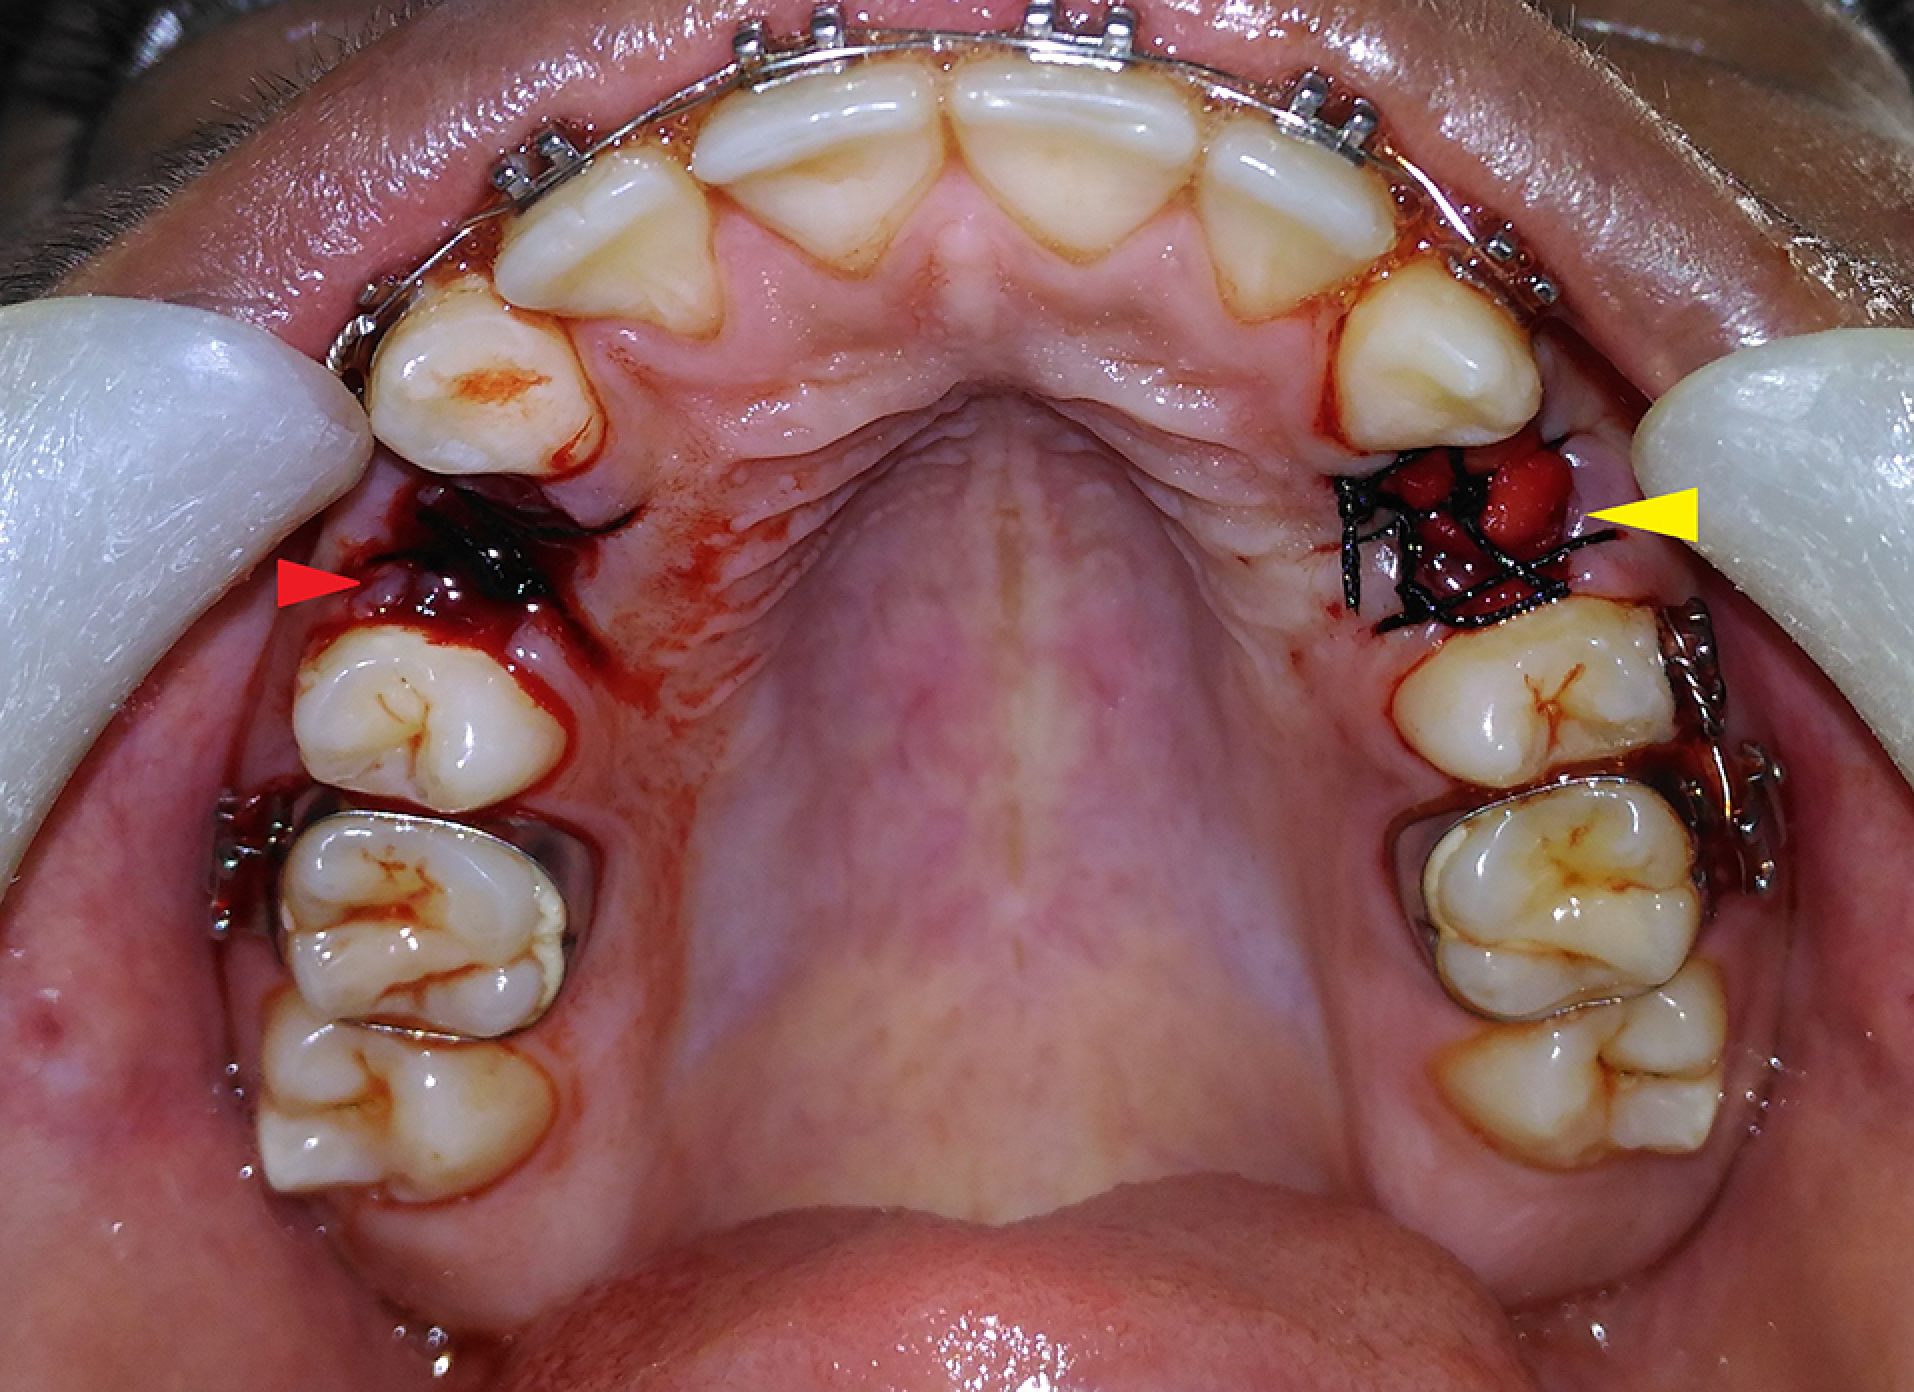

All the procedures were carried out under strict aseptic conditions. Following the administration of local anesthesia (2% LOX containing 2% lignocaine with 1:200000 adrenaline by Neon Laboratories Ltd.), the free gingival margin was elevated as conservatively as possible. The teeth were luxated using elevators and extracted atraumatically with forceps. After extraction, the sockets were carefully curetted. The patients’ arches (either maxillary or mandibular) were divided into quadrants and randomly labeled as test side and control side (in patients having even serial numbers, the right quadrant was labeled as the test side, and in patients with an odd serial number, the left quadrant was labeled as the test side). A collagen plug (KOLSPON PLUG) was inserted up to the crestal level in the extraction socket of the test side after saturating it with activated PRP and sutured into position using 3-0 silk sutures in the simple interrupted pattern. On the control side, the extraction socket was just sutured using 3-0 silk sutures in a simple interrupted pattern without placing any graft material (Figure 2). The width of the alveolar socket at the extraction site was measured using bone calipers at three levels (crestal, mid-root, and apical), immediately after extraction and after 3 and 6 months. A digital radiograph (RVG) was taken in combination with a radiopaque millimeter-graduated grid to evaluate the baseline bone height immediately after extraction and after 3 and 6 months. The extraction of the tooth and radiographic assessment were carried out by two different operators. The patients were given routine antibiotics and analgesics (Amoxicillin tablets, 500 mg TID, and Diclofenac sodium tablets, 50 mg BD for three consecutive days) and recalled 10 days after the surgery for suture removal and evaluation of soft tissue healing according to Landry, Turnbull, and Howley index.20

Postoperative photograph showing sutured grafted and non-grafted sites. [Patient’s right side, non-grafted site (red arrow), and left side, grafted site (yellow arrow).